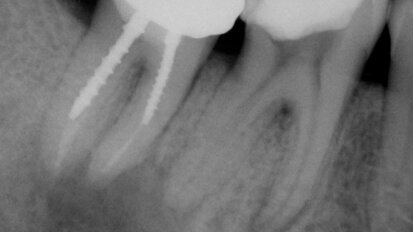

Retraitement endodontique : traiter ou ne pas traiter ?

La reprise de traitement endodontique décourage certains, désespère les autres. Cet article démontre la parfaite validité...